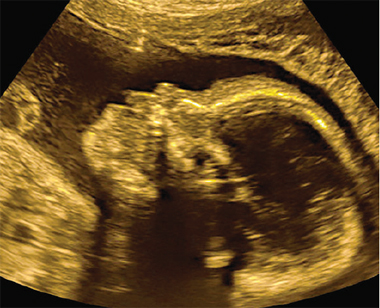

The study reports effects similar to developmental disorders such as ADHD or autism. |

If a mother is prescribed 17-OHPC, developing infants may be exposed to the hormone during critical periods of cortical development. Willing and Wagner used a rodent model to test the effects of 17-OHPC during development on cognitive flexibility — the ability to change strategy in light of shifting environmental contingencies — a process which they point out is highly dependent on dopaminergic activity in the prefrontal cortex. Rats were trained to use a rule to find a food reward, and then the rule was changed, so the rats had to shift to the new rule to find the food reward again.